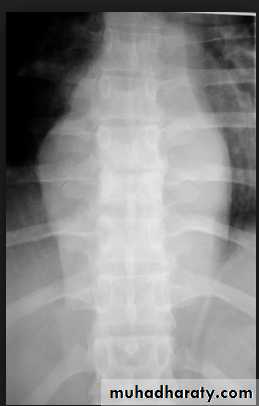

The plain film shows features which are typical for spinal tuberculous disease.

There is an extensive paraspinal soft-tissue mass.

Detail in the underlying spine is poor but there is early crowding of ribs posteriorly, indicating early vertebral collapse.

(B) Coronal MR image of the thoracic spine demonstrates destruction of the intervertebral disc at the point where the paraspinal widening is maximal and this change is associated with alteration of signal from the vertebrae.